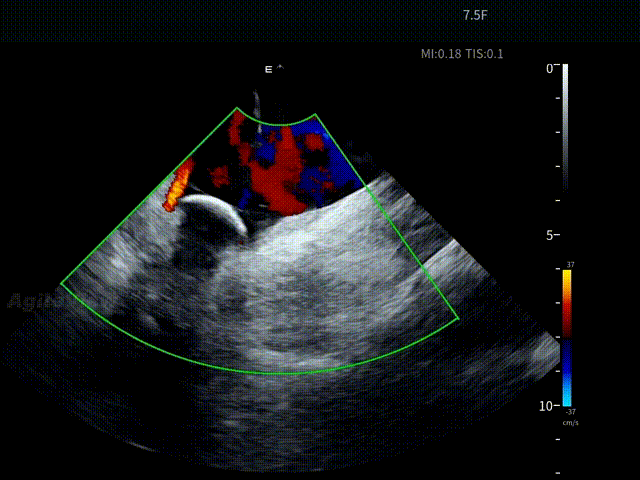

术中,基于AgileView™ 7.5Fr全球最细直径ICE导管的产品优势,周纬教授选择将ICE送入左房,以便更好地进行冷冻球囊的贴靠与位置的判断,在AgileView™ ICE实时影像的指导下, Arctic Front Advance Pro冷冻球囊导管消融导管安全进入左心房,先后完成双侧肺静脉隔离及顶部线隔离, ICE下可见导管贴靠良好,整个消融过程顺利,消融时间仅约25分钟,得益于超声设备清晰的成像质量,在顶部线隔离的时候可借助多普勒模式清晰的观察到球囊与组织的贴靠程度。 整个手术流程在ICE影像的指引下顺利完成,术中患者耐受良好,生命体征保持平稳。

ICE确认LSPV位置——B Mode

ICE确认LSPV位置——C Mode